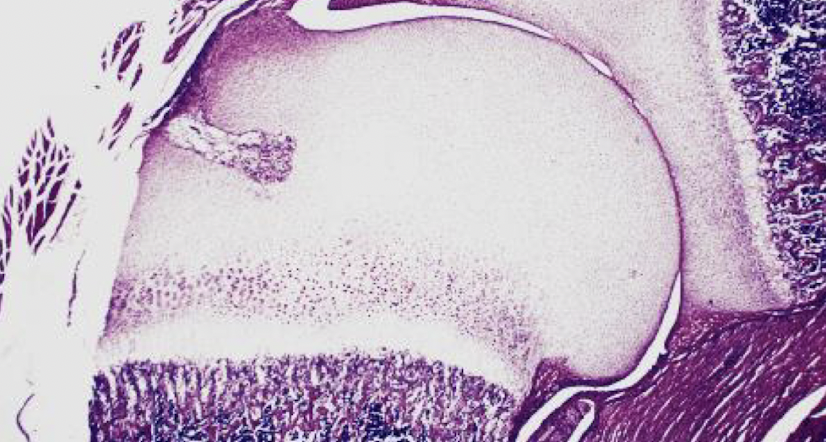

What is the process depicted in the image?

Intramembranous ossification